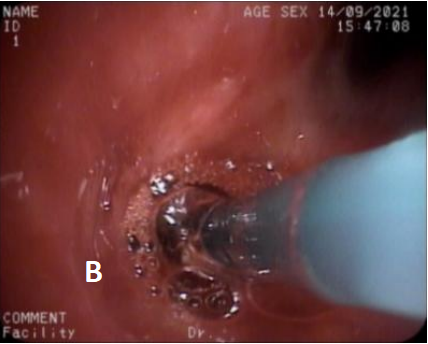

图4 第2次治疗(冷冻治疗+球囊扩张2021/9/14)

A. 冷冻治疗 B. 球囊扩张